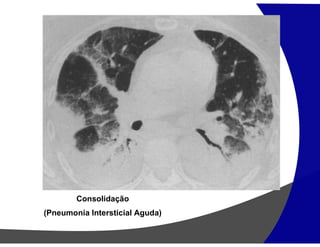

Consolidação

Preenchimento do espaço áereo apagando as estruturas

vasculares

Causas

• Edema: insuficiência cardíaca, SARA

• Hemorragia: trauma

• Pus: infecção (pneumonia)

• Células: tumores

• Lipoproteína: proteinose alveolar

(Pneumonia Intersticial Aguda)